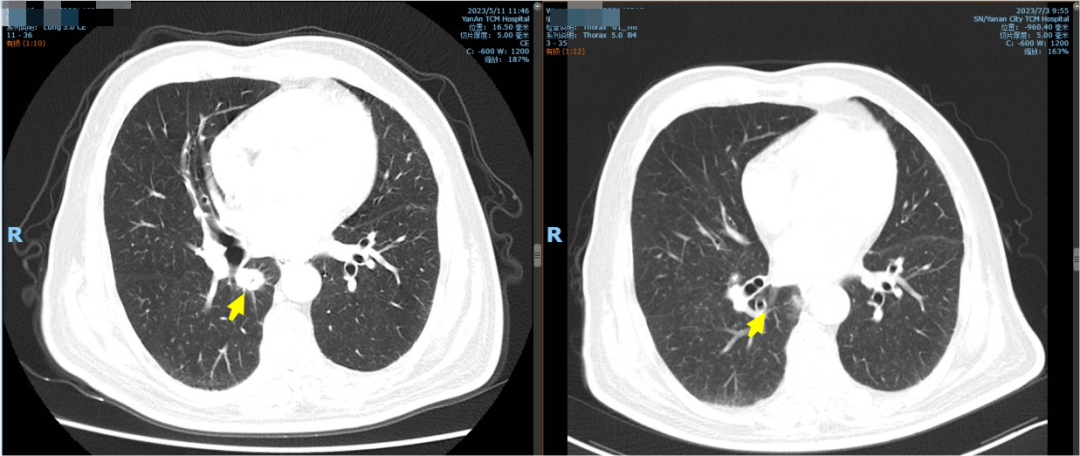

左图为射波刀治疗前,右图为射波刀治疗后

在确定治疗方案,告知患者及家属并征得同意后,我院立即启动了延安——北京转诊绿色通道,患者在延安完善胸部增强CT,支气管镜检查等相关检查后,5月份前往北京大学第三医院放疗科,考虑患者双肺病灶存在双原发的可能,为患者右肺病灶进行了射波刀治疗,接受治疗后患者胸部局部不适感减弱,且未出现不良反应,于是返回延安休养,等待下一步治疗。肿瘤科主任尹文琤说:“患者返回延安后继续在肿瘤科接受免疫维持治疗并行胸部增强CT检查,CT示右肺病灶符合射波刀局部治疗后影像学表现,目前患者肺部病情稳定。”